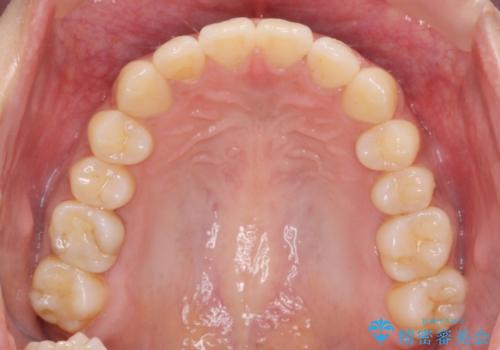

前歯のがたつきをすっきり マウスピース矯正

しっかりと前歯のがたつきは改善し見た目が大きく良くすることができました。

- 1年2ヶ月